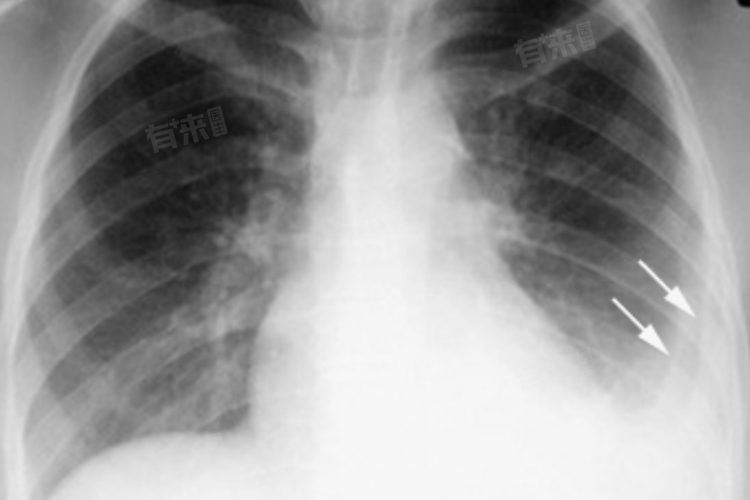

肺部DR(数字X线成像)和CT(计算机断层扫描)是两种不同的影像学检查方法,两者在肺部疾病的诊断中各有优势。关于肺部DR没事是否还需要做CT的问题,主要取决于患者的具体情况和医生的判断。

- 如果患者肺部DR检查没事,但出现了上述不适症状,或者DR检查发现了某些可疑的阴影或异常,但无法确定其性质时,医生可能会建议进一步做CT检查。CT检查具有更高的分辨率和更清晰的成像效果,能够更准确地显示肺部的结构和病变情况,有助于医生做出更准确的诊断和治疗方案。